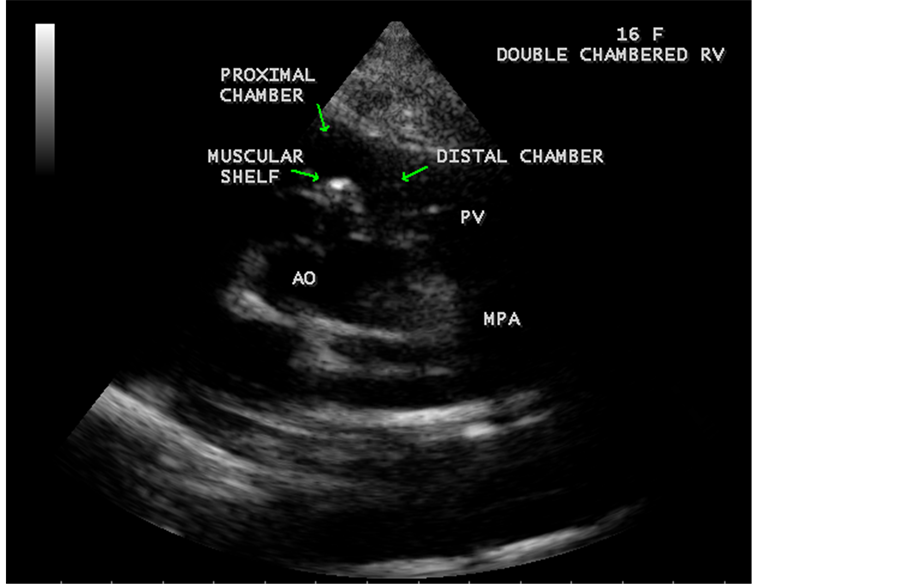

Figure 50. RV EMF in a 16-year-old female―associated with RVOT (RV outflow tract) disease― DCRV (double-chambered RV) as shown in Figure 51, Figure 52 and Figure 53.

Figure 51. Showing “Double chambered right ventricle” in a 16-year-old female.

Figure 52. Showing the muscular shelf of DCRV (double chambered right ventricle) in a 16-year- old female.

A left ventricular EMF mimicking apical left ventricular hypertrophic cardiomyopathy as shown in Figure 23, Figure 24 and Figure 25 in a 2-year-old male child and an apical right ventricular hypertrophic cardiomyopathy in a 60-year-old female as shown in Figure 26 mimicking as right ventricular EMF had been found by Transthoracic echocardiographic screening. A right ventricular EMF associated with Psoriasis was shown in Figure 3 to Figure 7 in a 52-year-old male and a left ventricular EMF associated with pemphigus skin lesion in a 63-year-old male as in Figure 40 were detected in this region of Thoothukudi. RV EMF associated with congenital heart diseases such as ostium secundum atrial septal defect in a 26-year-old female antenatally (Primi with 9 months amenorrhea) as shown in Figure 49 and Figure 64 to Figure 66 in a 9-year- old girl. RV EMF associated with RV outflow tract disease (“Double chambered right

ventricle”) in a 16-year-old female as shown in Figure 50 to Figure 53 were detected. RV EMF with rheumatic involvement of mitral valve as shown in Figure 54 and Figure 55 in a 44-year-old female and in Figure 63 in a 55-year old female. Biatrial enlargement due to rheumatic atrioventricular (AV) valves (mitral and tricuspid) involvement characterized by stenosis of the valves are illustrated in Figure 56 to Figure 59 in a 54-year-old female and it is differentiated from EMF which is characterized by AV valve regurgitation as shown in Figure 34 and Figure 60. RV EMF associated with thickening and fibrosis of moderator band in a 16-year-old female was shown in Figure 46. RV EMF associated with apical left ventricular hypertrophic cardiomyopathy was shown in a 47-year-old male as in Figure 61 and in a 65-year-old female as in Figure 62.